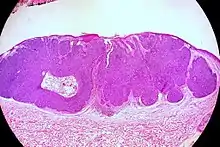

Nodular basal-cell carcinoma

Nodular basal-cell carcinoma (also known as "classic basal-cell carcinoma") accounts for between 50% and 80% of all BCC.[2] It most commonly occurs on the sun-exposed areas of the head and neck.[2] Histopathology shows aggregates of basaloid cells with well-defined borders, showing a peripheral palisading of cells and one or more typical clefts.[17] Such clefts are caused by shrinkage of mucin during tissue fixation and staining.[18] Central necrosis with eosinophilic, granular features may be also present, as well as mucin. The heavy aggregates of mucin determine a cystic structure. Calcification may be also present, especially in long-standing lesions.[17] Mitotic activity is usually not so evident, but a high mitotic rate may be present in more aggressive lesions.[17] Adenoidal BCC can be classified as a variant of NBCC, characterized by basaloid cells with a reticulated configuration extending into the dermis.[17]